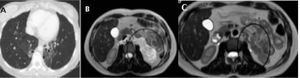

A: TC torácica. Bronquiectasias centrales y lobares de predominio en ambos LLII de aspecto quístico en LII con pérdida de volumen asociado. B: RMN de abdomen. Lesión retroperitoneal de al menos 80×95mm (T×L), hiperintensa en pT2 con presencia de tabiques en su interior y zonas con restricción de difusión y captación de contraste que sugieren componente sólido. C: RMN de abdomen. Práctica resolución de la masa quística retroperitoneal, con tamaño actual de unos 12×35×34mm.

A los 6 meses en la resonancia magnética de control se aprecia una mejoría con práctica resolución de la masa quística retroperitoneal, sin cambios significativos a nivel pulmonar (fig. 1D). El estudio de función respiratoria de control muestra mejoría con respecto al previo en cuanto al FEV1 (2.310ml-86%) y de la relación FEV1/FVC (0,74), no observando cambios en el resto de las variables.